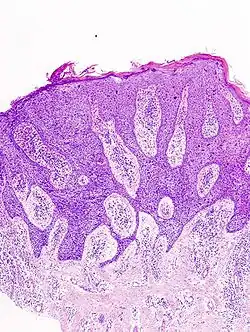

Histological characteristics

Histopathologically, the epidermis in cSCC in situ (Bowen's disease) will show hyperkeratosis and parakeratosis. There will also be marked acanthosis with elongation and thickening of the rete ridges. These changes will overly keratinocytic cells, which are often highly atypical and may have a more unusual appearance than invasive cSCC. The atypia spans the full thickness of the epidermis, with the keratinocytes demonstrating intense mitotic activity, pleomorphism, and greatly enlarged nuclei. They will also show a loss of maturity and polarity, giving the epidermis a disordered or "windblown" appearance.

Two types of multinucleated cells may be seen: the first will present as a multinucleated giant cell, and the second will appear as a dyskeratotic cell engulfed in the cytoplasm of a keratinocyte. Occasionally, cells of the upper epidermis will undergo vacuolization, demonstrating an abundant and strongly eosinophilic cytoplasm. There may be a mild to moderate lymphohistiocytic infiltrate detected in the upper dermis.[12]

Squamous-cell carcinoma in situ, showing prominent dyskeratosis and aberrant mitoses at all levels of the epidermis, along with marked parakeratosis.[12]